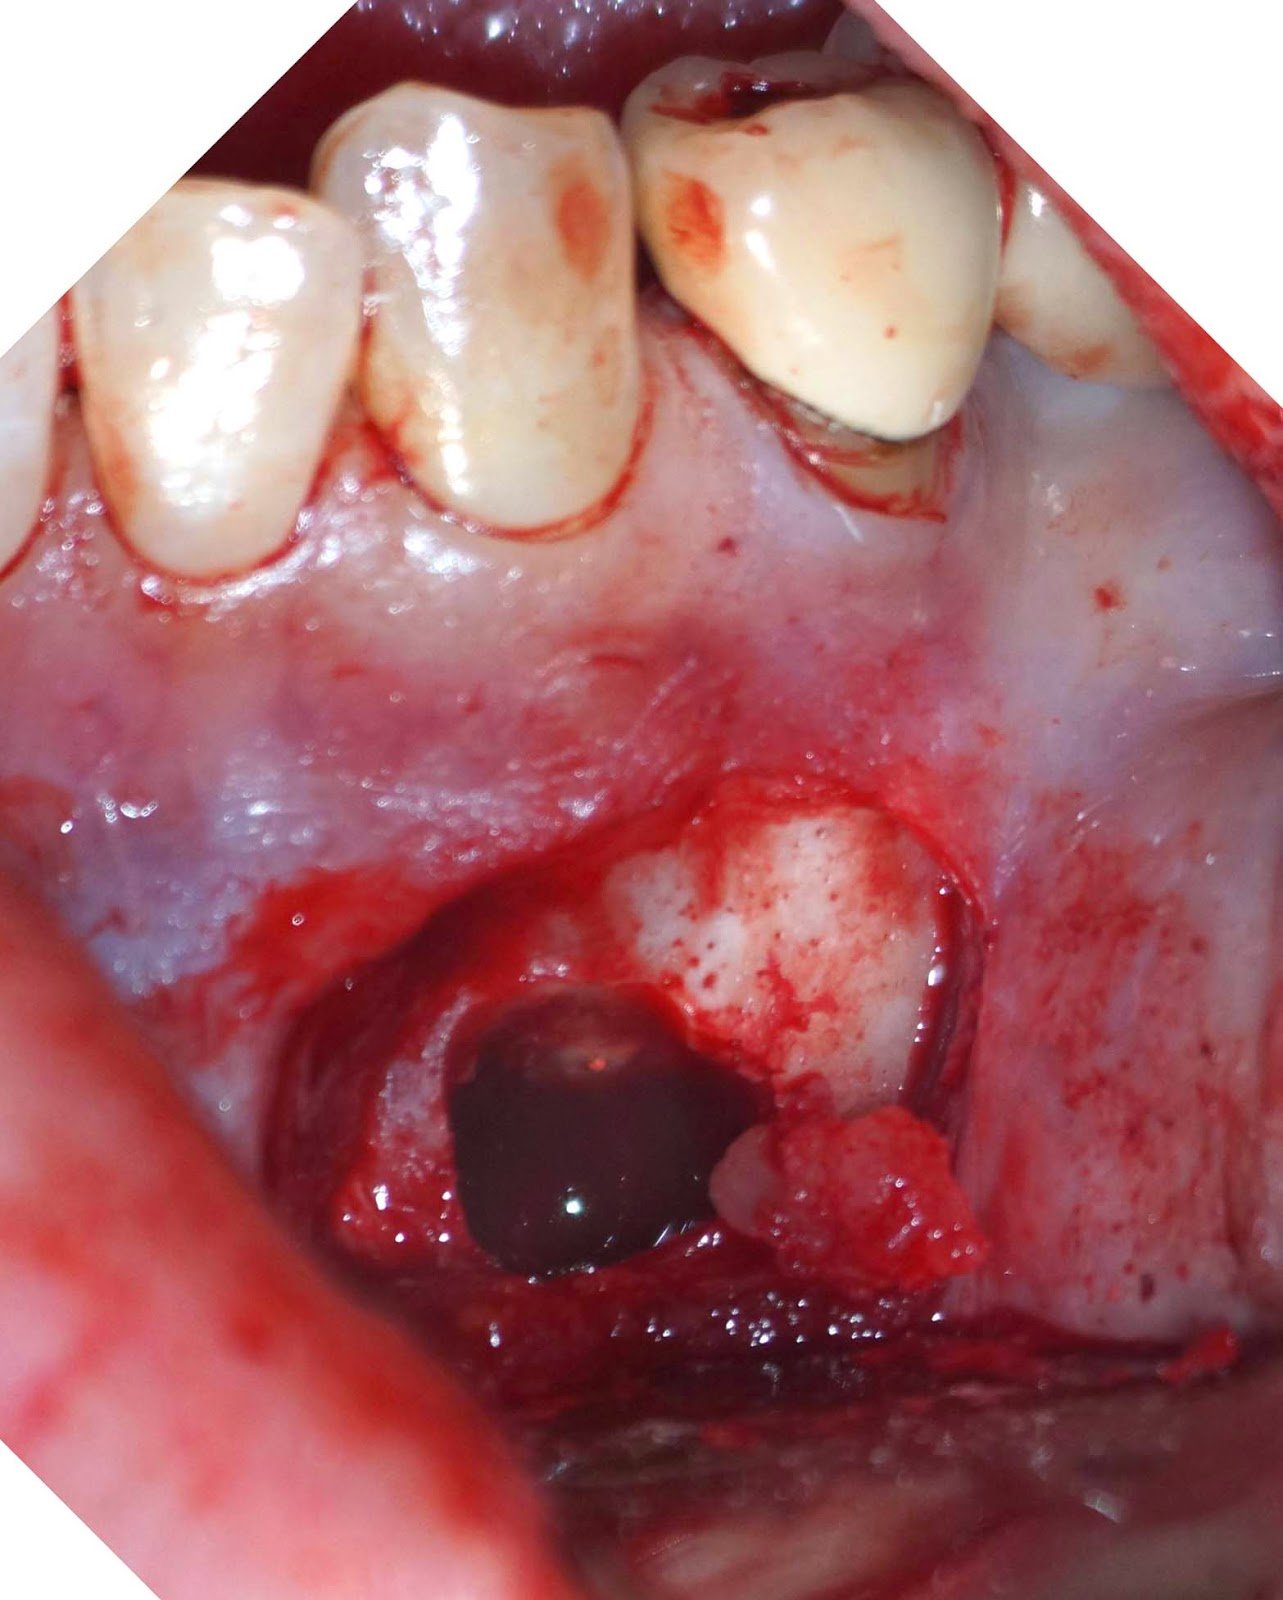

DX: Prior RCT with possible periapical cemental dysplasia. Apical surgery recommended with biopsy.

Biopsy report indicated Periapical Cemental Dysplasia (anterior focal osseous dysplasia) Recurrence would be unusual, but other areas of dysplasia can arise as well as truamatic bone cysts are also common.